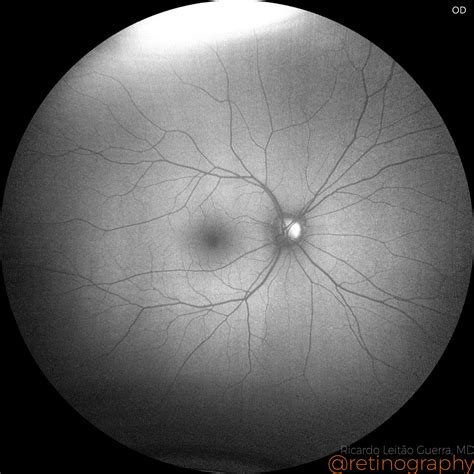

Fundus Autofluorescence (FAF): Because these calcium deposits are naturally fluorescent, FAF imaging can highlight them vividly, making it much easier to distinguish drusen from other tissue structures.

When you undergo a routine eye exam, your optometrist or ophthalmologist uses specialized equipment to peer into the back of your eye, focusing on the optic nerve head. Occasionally, they may notice small, glistening deposits that appear slightly elevated or irregular. These findings are often identified as Optic Nerve Drusen. While the term might sound intimidating, it is crucial to understand that in the vast majority of cases, these are benign, calcified deposits that develop over time within the optic nerve head itself. Although they are generally harmless, their presence can sometimes mimic other, more serious conditions, necessitating a clear understanding of what they are, how they are diagnosed, and when they require clinical attention.

• Disc appearance: During an ophthalmoscopy, the doctor will observe a “bumpy” or “mulberry-like” appearance on the optic nerve head, especially if the drusen are superficial.